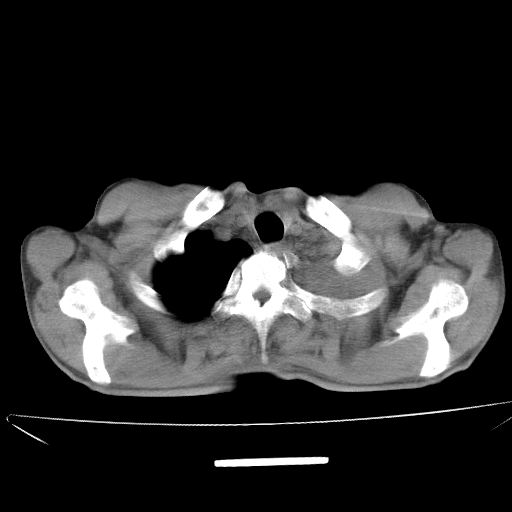

以下是引用杀毒软件在2009-4-28 17:58:00的发言:[br]考虑----左肺慢性肺脓肿形成继发上叶含气不良---抗炎后复查---待排肿瘤所致[br][br][本贴已被 杀毒软件 于 2009-4-28 18:01:26 修改过]